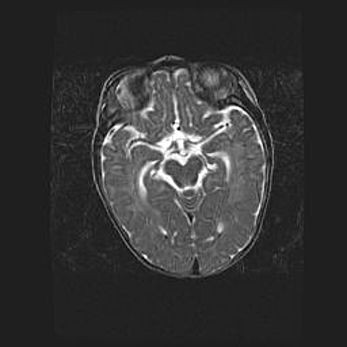

Подострая гематома правой гемисферы мозжечка.

Наружная гидроцефалия.

Возраст: 15 дней

Вес: 3100 г

Пол: женский

Окружность головы: 37 см

Срок гестации: 35-36 недель

При открытой наружной форме гидроцефалии у новорожденных расширяются и переполняются субарахноидные пространства.

Кровоизлияния в мозжечок имеют две клинико-анатомические формы: полушарные гематомы и кровоизлияния в червь.

К появлению этой патологии может привести: повреждения головного мозга, возникающие в результате асфиксии и гипоксии плода при беременности, или травмы во время родов. Редко гематома мозжечка может быть результатом первичной коагулопатии и сосудистой мальформации, диссеминированном внутрисосудистом свертывании, изоиммунной тромбоцитопении.